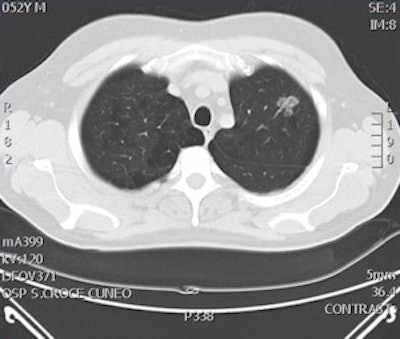

Digital tomosynthesis detected a left apical nodule in a 52-year-old male smoker. All images courtesy of Stephane Chauvie, PhD, and Dr. Maurizio Grosso.

CT confirmed the nodule in the patient and consequently he underwent surgery, which confirmed the tumoral nature of the nodule."We have very preliminary data, but we believe digital tomosynthesis is a quite good method of detection for nodules," Grosso said.